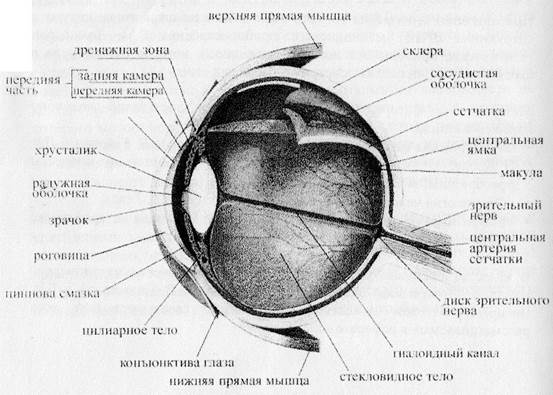

КТ-графики и изображение строения глаза